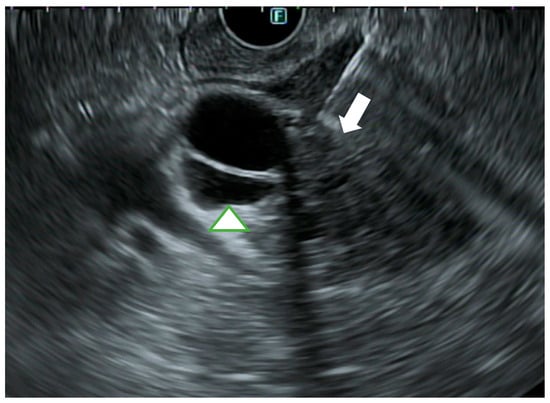

3.2. EUS

3.3. Intraductal Ultrasound (Miniprobe Endoscopic Ultrasound)